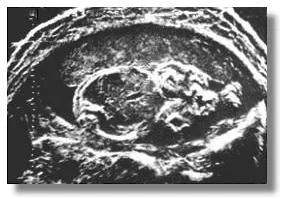

UI Octoson представлял собой простейший эхоскоп с ванной для сканирования, на мембране которого находился пациент. Внутри ванны были размещены 8 круглых ультразвуковых передатчиков, образующих фазированную ультразвуковую решетку, которая приводилась в движение механическим приводом-качалкой. Получаемые прибором изображения были поистине впечатляющими и существенно превосходили результаты труда конкурирующих рабочих групп из Европы.